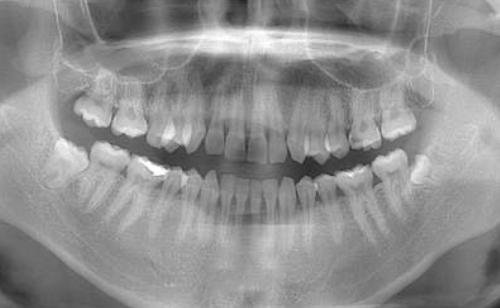

| 年齢 | 56歳・男性 |

|---|---|

| 主訴 | 定期検診 |

| 治療内容 | 歯周基本検査・歯石除去・着色除去・フッ素塗布 |

| 治療期間 | 60分 |

| 費用 | 保険診療約4,500円 (歯の本数や検査内容で料金が変動します。) (2023/12/25時点の価格) |

| リスク・副作用 | ・歯ぐきの炎症がある場合は歯石除去中に出血を伴う可能性があります。 ・処置後に歯がしみることがあります。 ・歯ぐきの炎症が軽減すると歯ぐきが引き締まり、歯が長く見えることがあります。 ・定期検診は予防の一環であり、検診の来院で必ず虫歯や歯周病にならない訳ではありません。 |

| 担当者所見 | ブラッシング指導後、歯石除去を行い定期検診へ移行 矯正治療を行う予定 |

| 特記事項 | 交叉咬合・かみ合わせが強い |

| 担当者所見 | 初診時は歯石が全顎的に付着しており、歯石除去時は出血もありました。特に下の前歯は歯と歯の間を埋めるように多量の歯石が付着していました。ブラッシング指導も行い、定期検診へと移行しました。 定期検診時は全体的な清掃状態も良好で、ご自身も歯ブラシを頑張っているとおっしゃっていました。矯正治療開始後も綺麗で健康な口腔内を維持する為、定期検診を継続的に行っていく予定です。 |